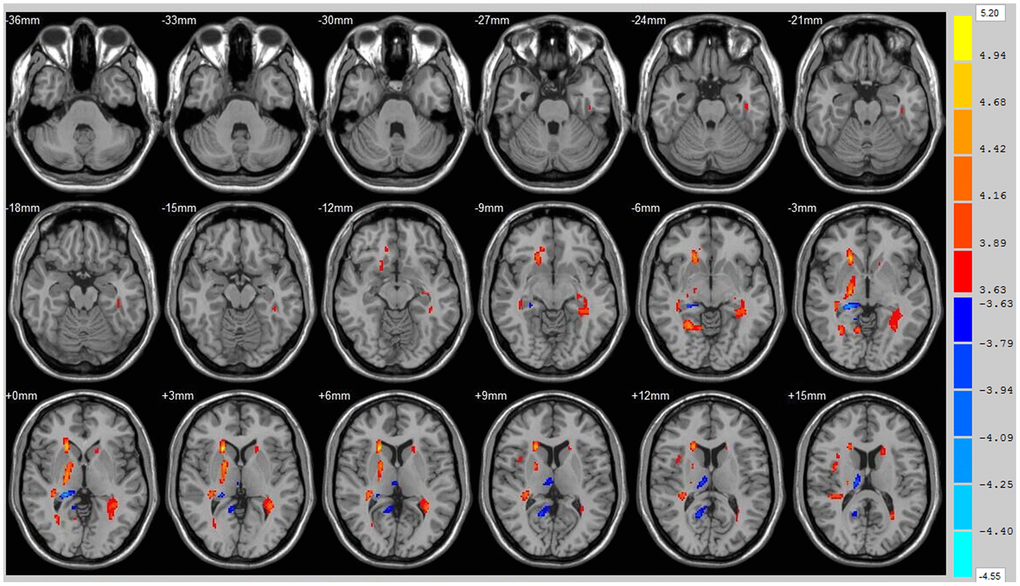

Using the whole brain analysis, we found that 1 week after ICH, patients displayed lower FA values in two brain clusters that included the ipsilateral temporal lobe, frontal lobe, insula, lenticular nucleus, putamen, caudate nucleus, hippocampus and thalamus than did the controls (Figure 1 and Supplementary Table 1). Two clusters with decreased FA values were also observed at week 12 (Figure 2 and Supplementary Table 2). Moreover, 12 weeks after ICH, six clusters (ipsilateral frontal lobe, lenticular nucleus, caudate nucleus, putamen, globus pallidus, and the contralateral parietal lobe, temporal lobe and hippocampus) exhibited higher FA (Figure 3, orange and Supplementary Table 3) while two clusters (ipsilateral limbic lobe, posterior cingulate gyrus and hippocampus) exhibited lower FA than at week 1 (Figure 3, blue and Supplementary Table 4).

Figure 3. Brain areas with decreased FA value of ICH patients at 1st w and 12th w. Brain areas with increased FA value (Orange) and decreased FA value (Blue) of ICH patients at 12th w compared with 1st w, Threshold=3.6335.